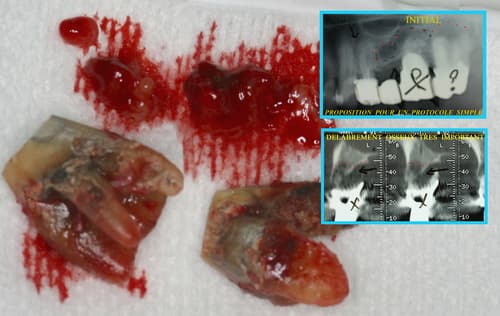

Le laser peut également intervenir dans la préparation des sites osseux après extraction, afin de favoriser la régénération et préparer la pose implantaire.

Per-opératoire

Post-opératoire